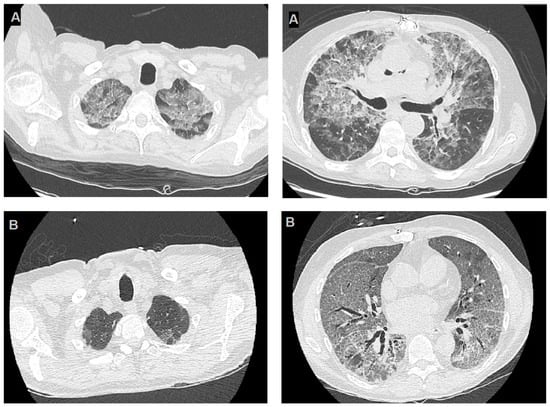

| Imaging: | Case 1 | Case 2 |

| Chest X-ray: | Diffuse alveolar-interstitial opacities, possible pulmonary oedema | Diffuse bilateral thickenings |

| RCT: | Multiple symmetrical ground-glass opacities. Apical and perihilar prevalence. | Ubiquitous ground glass thickenings. Anterior–posterior gradient. |